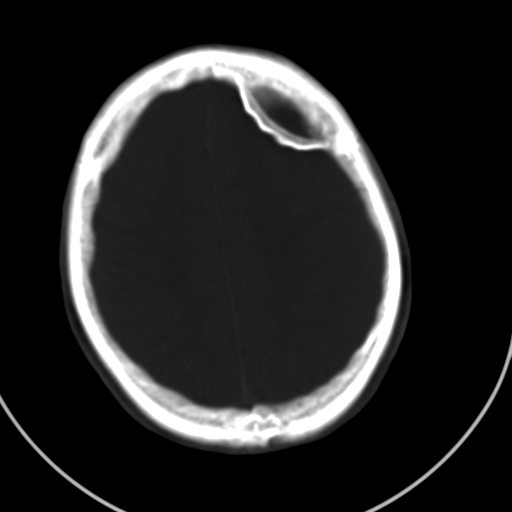

标题: CT21939:男20岁,外伤一年后,现头疼. [打印本页]

标题: CT21939:男20岁,外伤一年后,现头疼.

考虑硬外血肿并血肿肌化? 难道是传说中的盔甲脑?

左侧额部硬膜外血肿机化、骨化。

颅内的贝壳就是这样形成的。

左侧额部硬膜外血肿机化、骨化